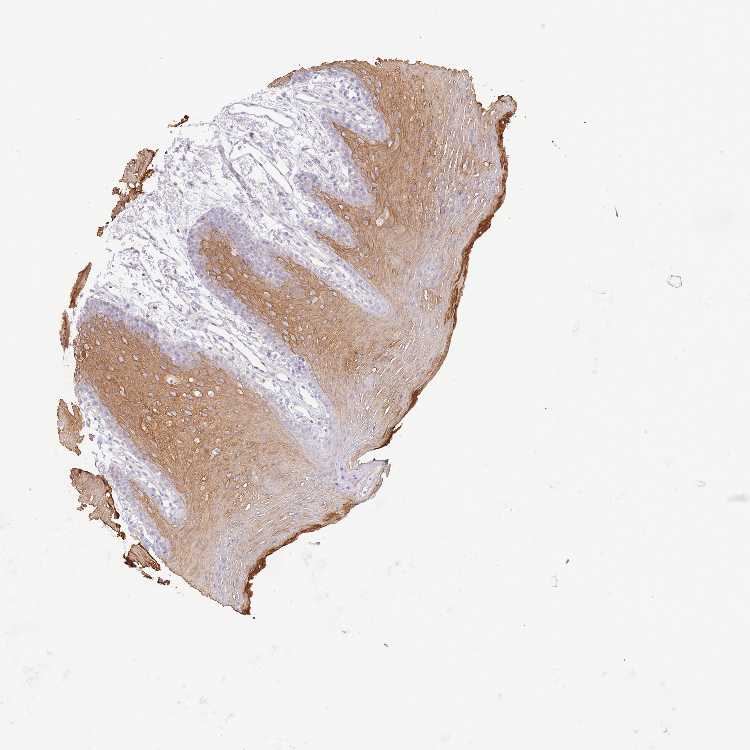

TISSUE PRIMARY DATA ORAL MUCOSA Show tissue menu

ORAL MUCOSA - Antibody stainingi

Antibody staining in the annotated cell types in the current human tissue is reported as not detected, low, medium, or high, based on conventional immunohistochemistry profiling in selected tissues. This score is based on the combination of the staining intensity and fraction of stained cells.

Each image is clickable and will lead to virtual microscopy that enables deeper exploration of all samples and also displays staining intensity scores, fraction scores and subcellular localization as well as patient and tissue information for each sample.

Antibody HPA044158Antibody HPA047913

Squamous epithelial cells Not detectedLow